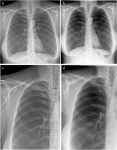

Согласно исследованию, опубликованному 18 февраля в журнале European Radiology , экспериментальная система рентгенографии грудной клетки в темном поле может получать диагностические рентгеновские […]… далее